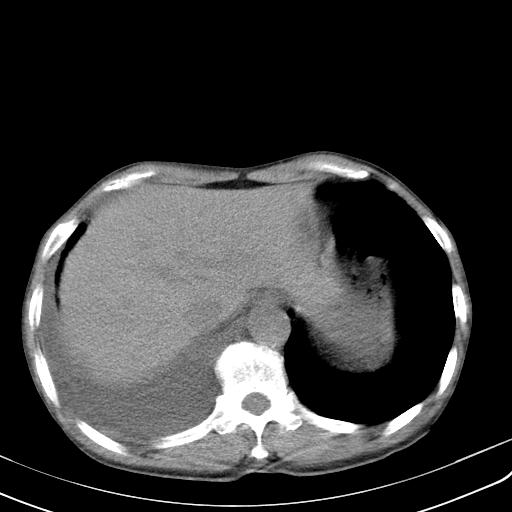

男性 75  咳嗽 一周前发热最高达39

右肺继发型tb并右侧tb性胸腔炎,右侧胸腔大量积液并右下肺膨胀不全,慢支肺气肿、多发肺大泡。建议抽胸水实验室检查并复查排除恶性在占位。

右上肺继发型肺结核,右胸腔中等量积液。

补充材料,患者2月份ct片大致正常,双侧胸腔积液,2月份抽胸水未发现ca细胞,现患者发热,痰多,各气管通畅,

1)右肺继发型肺结核。2)左肺胸膜下多发性肺大泡。3)右侧胸腔积液。